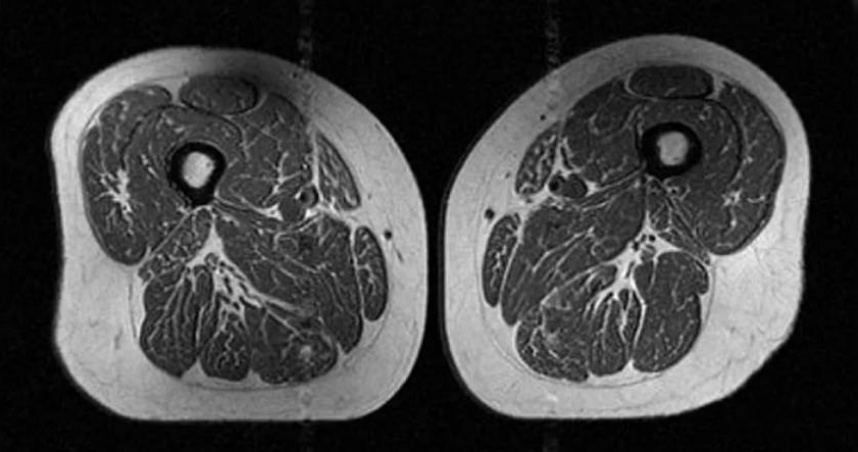

圖為一名年約60歲女性的大腿肌肉,其攝取超加工食品佔一天總熱量的87%。(圖/翻攝自Radiological Society of North America)

蔡明劼PO出研究中的核磁共振影像,照片中比較2名BMI相近的女性,左圖的女性,攝取超加工食品佔一天總熱量的29.5%;右圖的女性則攝取87.1%,「儘管兩者的BMI相近,腰圍以及大腿油花指數竟然有天壤之別」。

蔡明劼表示,這種現象在男女身上都一樣明顯,代表攝取超加工食品會導致肌肉品質下降。蔡明劼說明,大腿肌肉功能對於膝關節的穩定性至關重要,一旦肌肉品質被脂肪取代,支撐力就會下降,導致肌力衰退、走路速度變慢,進而影響整體的活動能力,還可能引發發炎反應及功能性影響,進一步損害關節健康。另外,研究也發現,考量到反映內臟脂肪分布的中央型肥胖,腰圍與大腿肌肉脂肪的關聯性比看BMI更明顯。